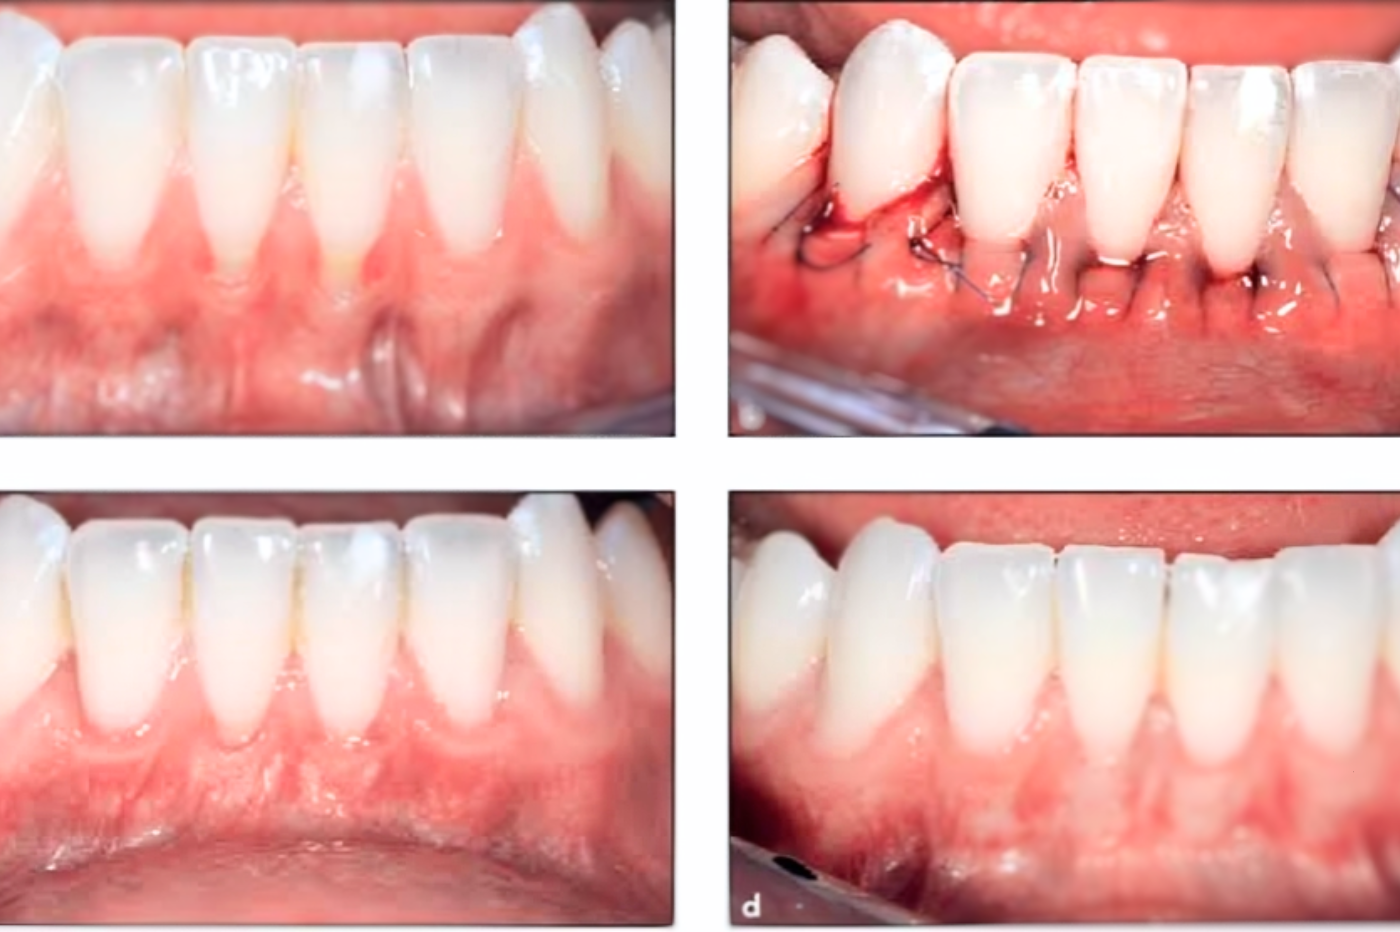

Gum surgeries are dental procedures aimed at treating various gum-related issues, such as gum disease or gum...